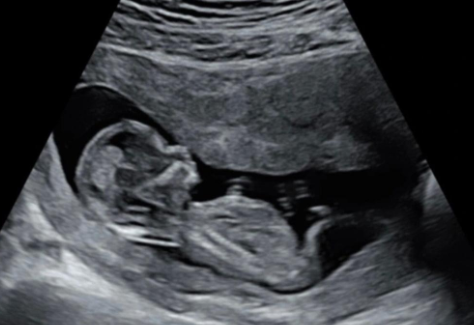

超声在介质中传播时,界面会产生反射信号。比如人体内部脂肪、血液、内脏器官、肌肉等对超声的反射强度均不同,这跟生物组织的声阻抗有关。仪器设备会根据反射信号的时间(深度)和幅度(灰度)进行成像,就能得到B超图像了。

超声检测往往需要涂耦合剂,因为探头与被检测物体之间的空隙会将超声全部反射回来,能量无法继续深入。做B超时涂耦合剂(皮肤上涂抹的粘液)的原因就是要排出皮肤与探头之间的空气,此外,耦合剂还能润滑探头与皮肤,使探头可以在皮肤表面顺滑地移动。